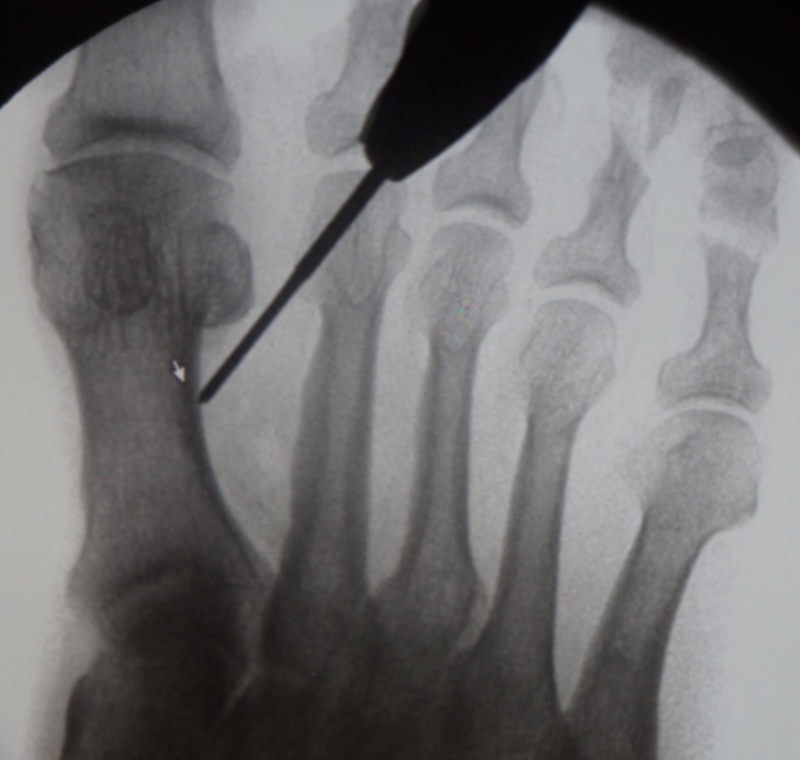

• Bildverstärker für intraoperative Kontrollaufnahmen 3.

• Bildverstärker.

• Gegebenenfalls röntgendichte Handschuhe.

• Positionierung des Bildverstärkers im 90° Winkel zur Fußlängsachse (Abbildung 4).